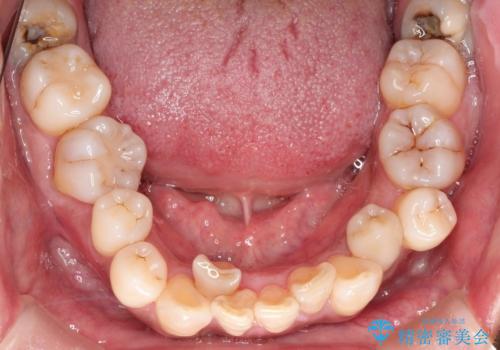

- 50代の患者様で、右上の八重歯と歯並びの乱れを気にされてご来院されました。特に、すでに装着されている前歯のセラミックブリッジを外したくないという強いご希望がありました。精密な検査の結果、八重歯を治すためのスペースが不足しているため、右上の4番目の歯(小臼歯)を抜歯し、そのスペースを利用して歯並び全体を整える治療計画を立案。装置には目立たないインビザラインを採用し、ブリッジを温存しながら八重歯の改善を目指しました。

今回の治療で最も重要だったのは、患者様のご要望通り既存のセラミックブリッジを外さずに矯正を進める点でした。計画通り右上の小臼歯を抜歯し、透明なインビザラインを使用して抜歯スペースを閉じながら、八重歯を正しい位置へ移動させました。ブリッジの形態と調和するに、他の歯の移動を工夫をすることで、複雑な条件をクリア。治療の結果、長年気にされていた八重歯が解消され、見た目が大きく改善しました。50代からでも、ご自身の要望を叶えながら、美しく機能的な歯並びを獲得していただけました。